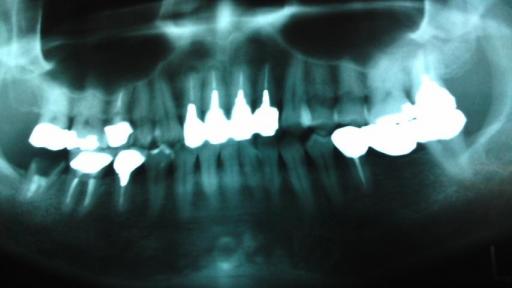

インプラントによる噛み合わせ構築法

奥歯で 全く噛めていませんでした。

左上の奥歯に3本 インプラントの土台が入りました。

左の奥歯が噛めるようになりました。 続いて 右下に2本のインプラントの土台が入りました。